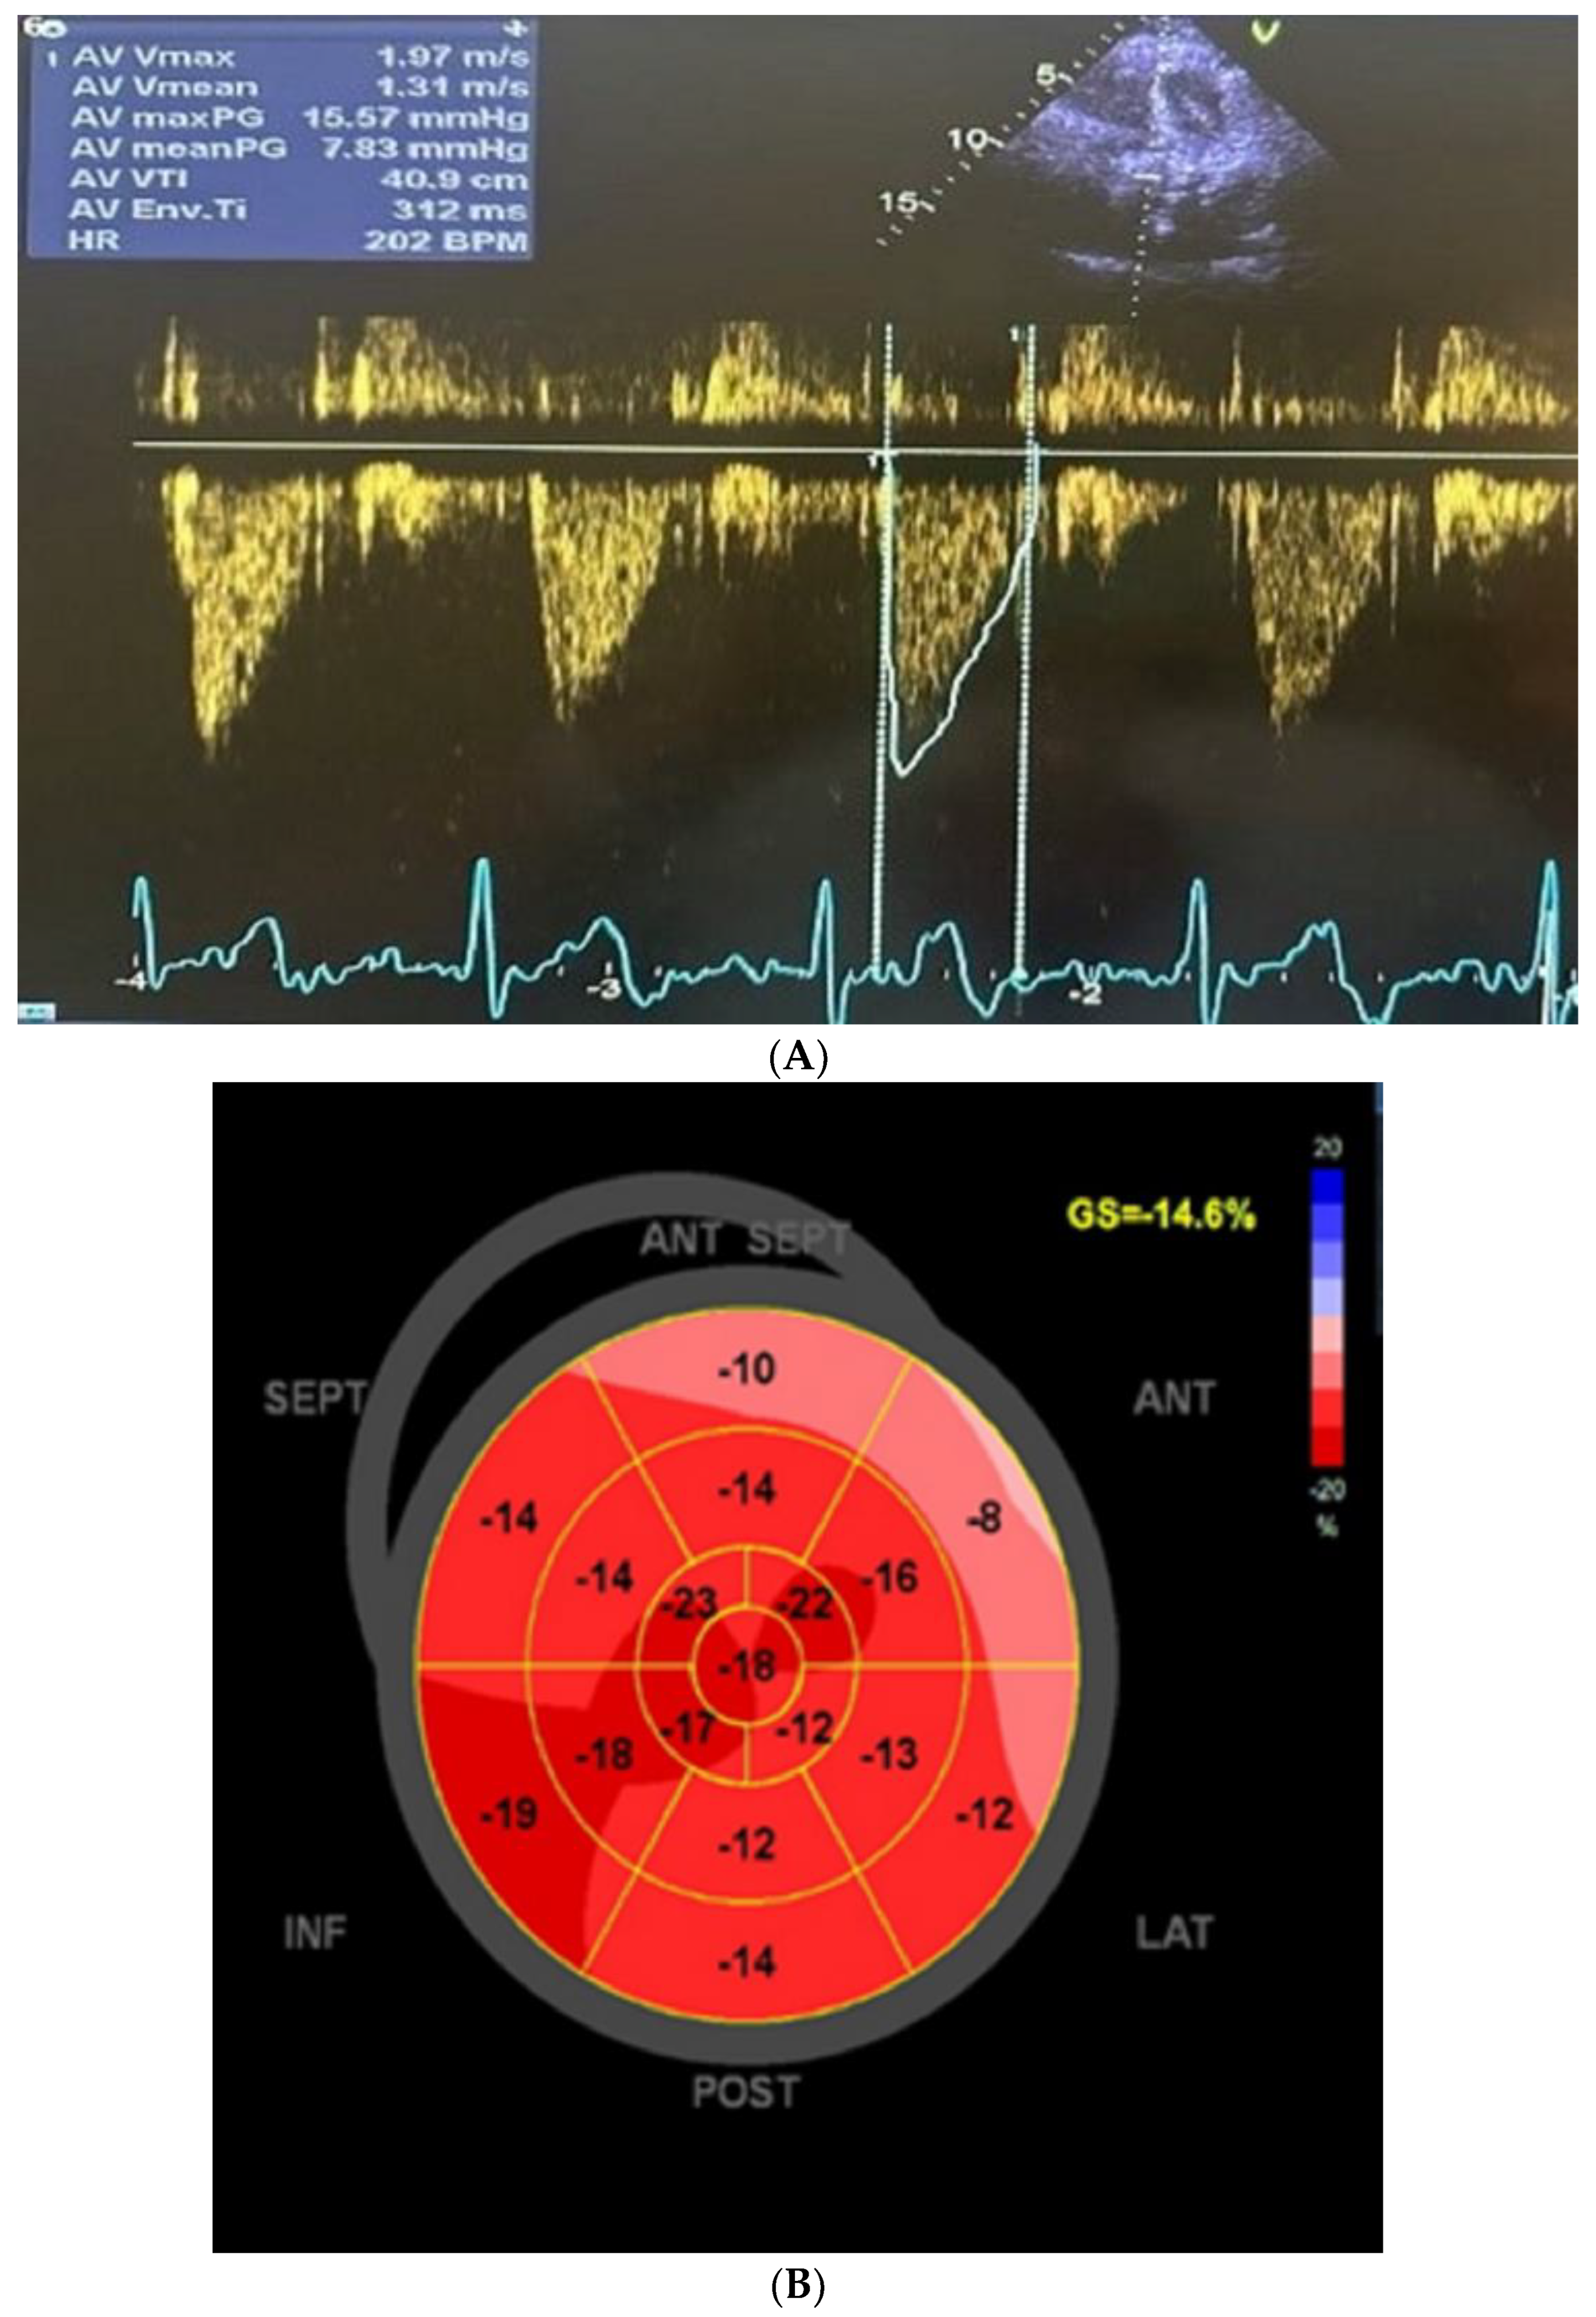

3. Cardiac Findings

4. Patient Management